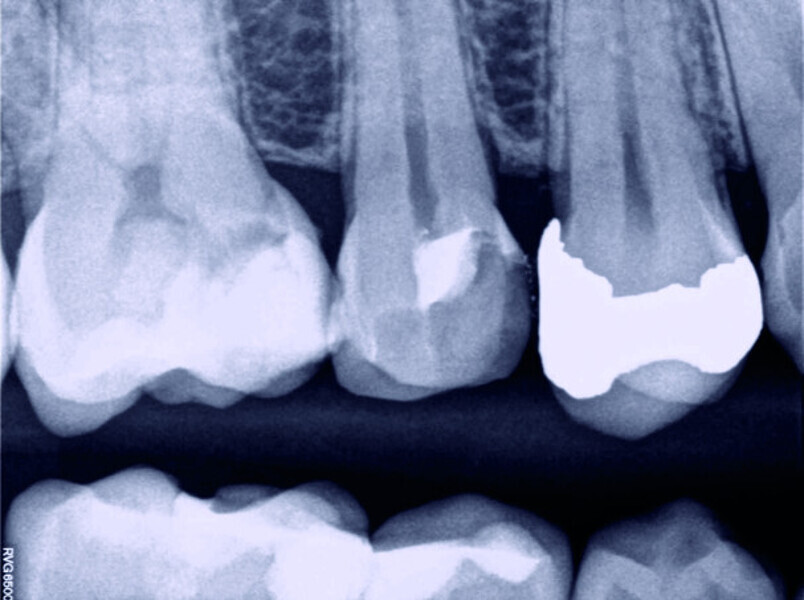

Direct pulp capping as a conservative procedure to maintain pulp vitality